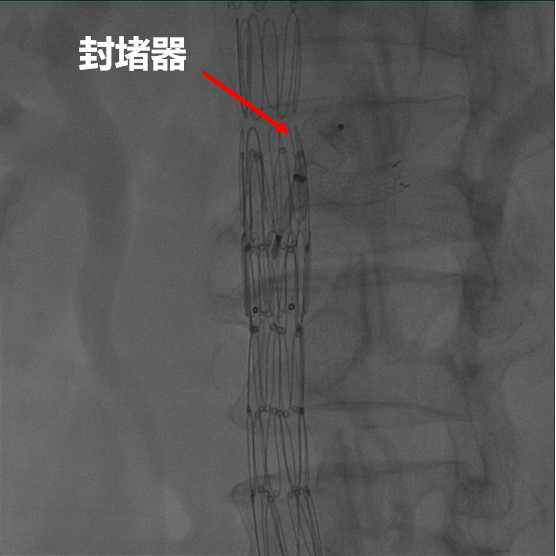

【病例3】B型夹层,TEVAR术后Ⅱ型内漏

复杂病例再干预方案:联合应用栓塞、覆膜支架及封堵器

术后四个月CTA

第二次术前造影,证实为LSA所致Ⅱ型内漏

LSA置入覆膜支架后造影,内漏消失